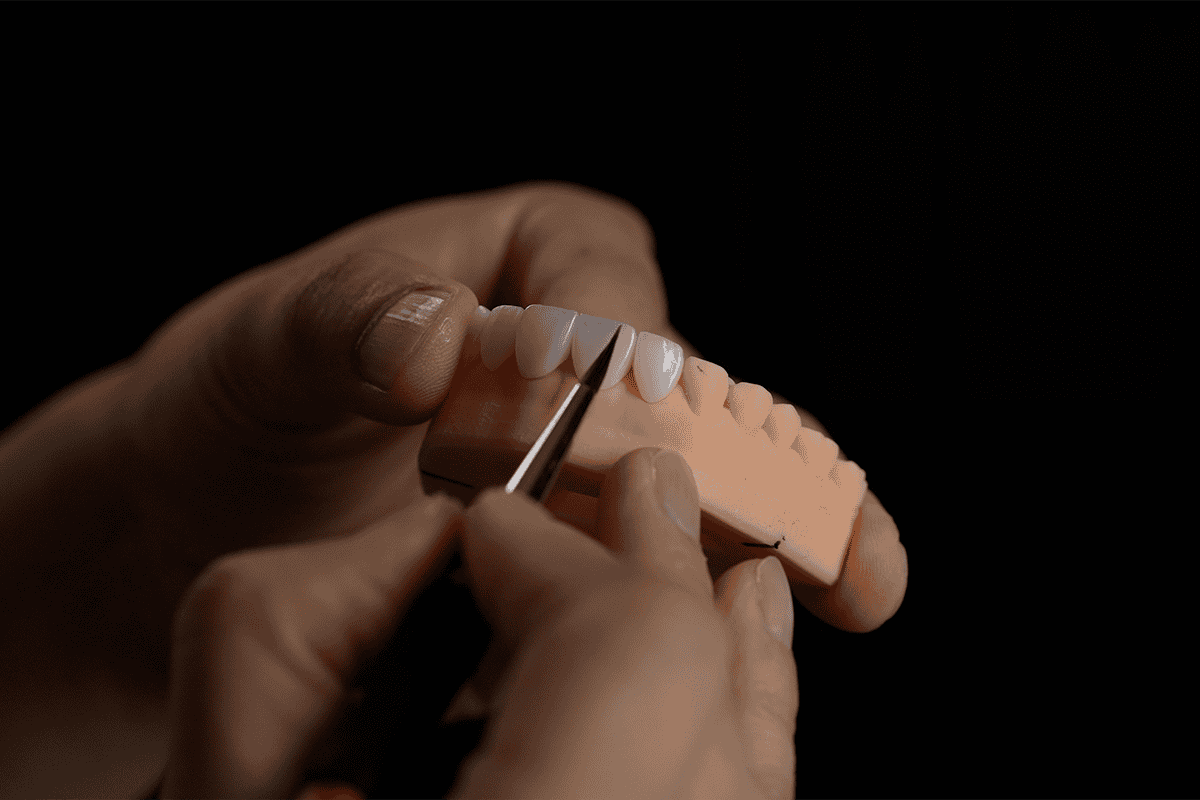

Veneers and dental implants

If you are experiencing negative effects from gum recession, the first port of call is visiting your dentist to determine the underlying cause and best course of treatment. Once poor oral hygiene is corrected, some great cosmetic treatments to restore your smile can be offered. This is where Advanced Dental Artistry’s porcelain veneers and dental implants come in.

Our hand-crafted porcelain veneers can help restore a more natural, uniform look to your smile with high-quality materials that fix the problem of yellowed, chipped, or cracked teeth. Our specially designed dental implants are the perfect solution for loose or missing teeth that can result from gum recession. The bespoke implants are expertly crafted to suit your face and mouth, providing you with a smile with a natural look and feel.